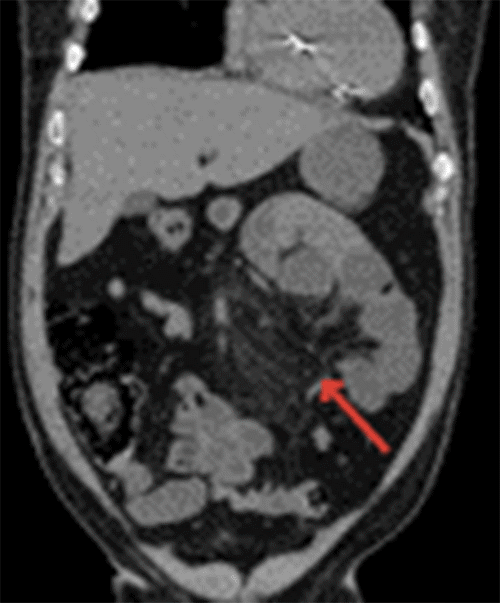

A noncontrast computed tomography (CT) scan of the abdomen obtained in the emergency department showed distended small bowel loops in the left upper quadrant that appeared clustered in the left pararenal space with mild crowding, congestion, and stretching of the mesentery suggestive of an internal hernia causing an acute intestinal obstruction (Figure 1). Given the presence of an acute abdomen, the patient was taken emergently to the operating room for abdominal exploration.

Figure 1. Coronal CT Scan of Abdomen. Published with Permission

A) Distended and clustered small bowel loops in left upper (arrow).

B) Crowding, congestion, and stretching of small bowel mesentery (arrow)

Given the challenges of clinical diagnosis of L-PDHs, diagnosis is based on pathognomonic features on CT scanning. The characteristic CT findings include an abnormal cluster or sac-like mass of dilated small bowel loops to the left of the ligament of Treitz and crowded, engorged, and stretched mesenteric vessels supplying the herniated small bowel segments.14,15